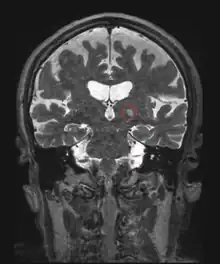

Le traitement des lésions intracérébrales par ultrasons focalisés est difficile en raison de la barrière osseuse (crâne), qui déforme les faisceaux ultrasonores. Les premiers tests, qui remontent aux années 1950 ont ainsi été réalisés à travers une ouverture pratiquée dans le crâne[15]. L'utilisation de réseaux de transducteurs avec correction numérique de la distorsion osseuse basée sur des données tomodensitométriques du crâne a permis de focaliser les ultrasons à travers un crâne intact[16] et d'expérimenter la technique sur des tumeurs cérébrales[17].

La destruction ou la section de certaines petites structures cérébrales par chirurgie stéréotaxique permet d'améliorer certaines maladies neurologiques. Les HIFU, guidées par imagerie par résonance magnétique[21] semblent être une alternative moins lourdes et ont été testées dans plusieurs maladies : douleurs neuropathiques (section du thalamus centrolatéral[22]), tremblements essentiels (thalamus[23],[24]) et maladie de Parkinson (faisceau pallidothalamique (en) [25].) La technique non invasive concurrente reste la radiochirurgie où la lésion est obtenue par un rayonnement radio-actif.